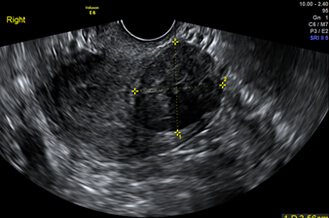

正常卵巢